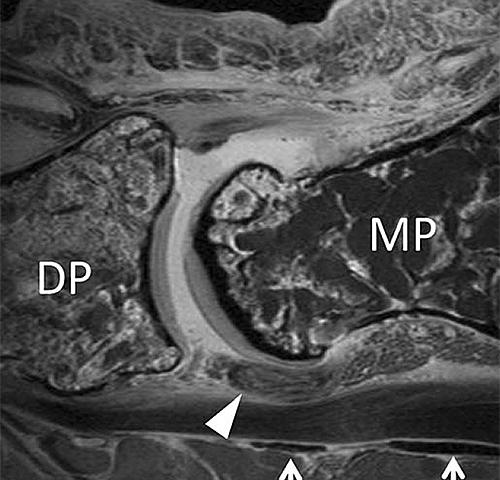

This article, published in Skeletal Radiology, characterizes in detail anatomic structures of the pulleys of the flexor tendons of human toes.